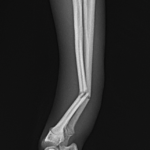

ドッグランで遊んでいた所、他のワンちゃんと接触して橈骨骨折をしたとのことでかかりつけ医より、若い子犬が紹介受診されました。橈骨骨幹部を1.5 Titanium Locking Plateで固定術を行いました。子犬には辛いですがしばらく安静が必要です。